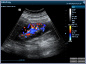

Neben einem ausführlichen Gespräch, der Anamnese, Zeit und Zuwendung gehören auch die Anwendung von wissenschaftlich evaulierten diagnostischen Verfahren zu einer guten Eingangsuntersuchung. Ich freue mich Ihnen in meiner Praxis deshalb nun auch die Ultraschalluntersuchung mit modernster Technik, einem mindray Consona N6 anbieten zu können.

- Darstellung der Schilddrüse - Darstellung der hirnversorgenden Gefäße mit Messung der Intimadicke (IMD) - Ultraschall des Herzens z. B. Stenose / Dichtigkeit der Herzklappen, Wandbewegungsstörungen,... - Ultraschall des Bauchraumes wie Leber, Gallenblase, Nieren, Blase, Milz. - Gefäßdarstellung

Video Farbdoppler der Halsarterie zur Darstellung der Durchblutung Video Farbdoppler der Niere zur Darstellung der Durchblutung Video Herzultraschall eines gesundes Herzens mit guter Pumpfunktion Video Herzultraschall mit eingeschränkter Pumpfunktion und vergrößerten Vorhöfen Video Herzultraschall bei Herzinsuffizienz und undichter Herzklappe